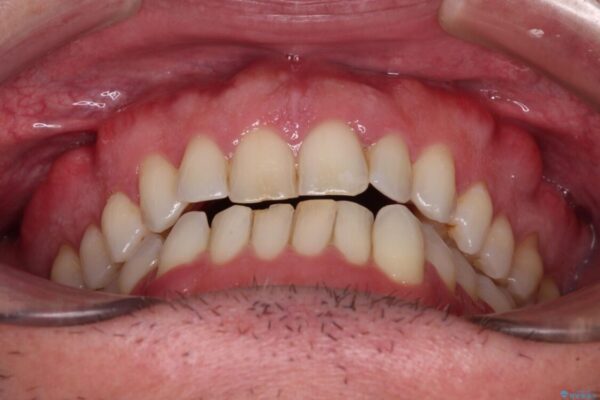

前歯でものを噛みきりたいとのことで来院された患者様です。

以前矯正治療を経験されたそうですが、舌の突出癖により上下前歯に隙間ができている様子でした。

治療前

• 前歯でものを噛みきりたい 目立たない装置でのワイヤー矯正 治療前画像